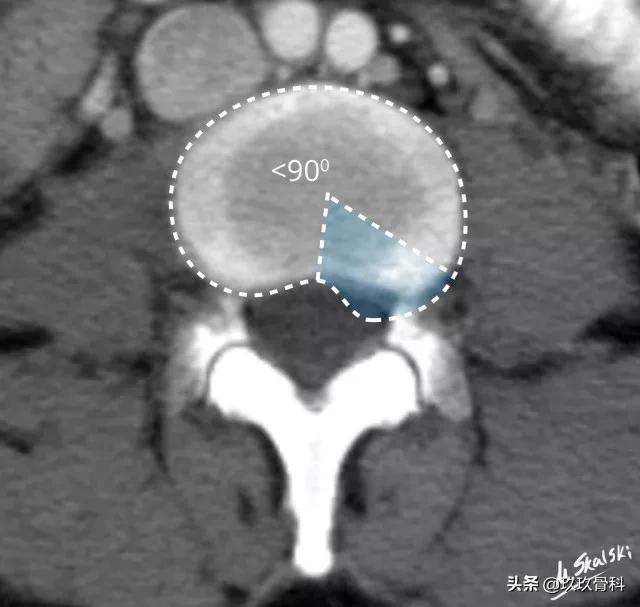

图 4 椎间盘突出的影像学定义为突出部分小于椎间盘边缘的25%,并且基底部>突出部分的直径;突出椎间盘的两边与髓核的中心的夹角<90°